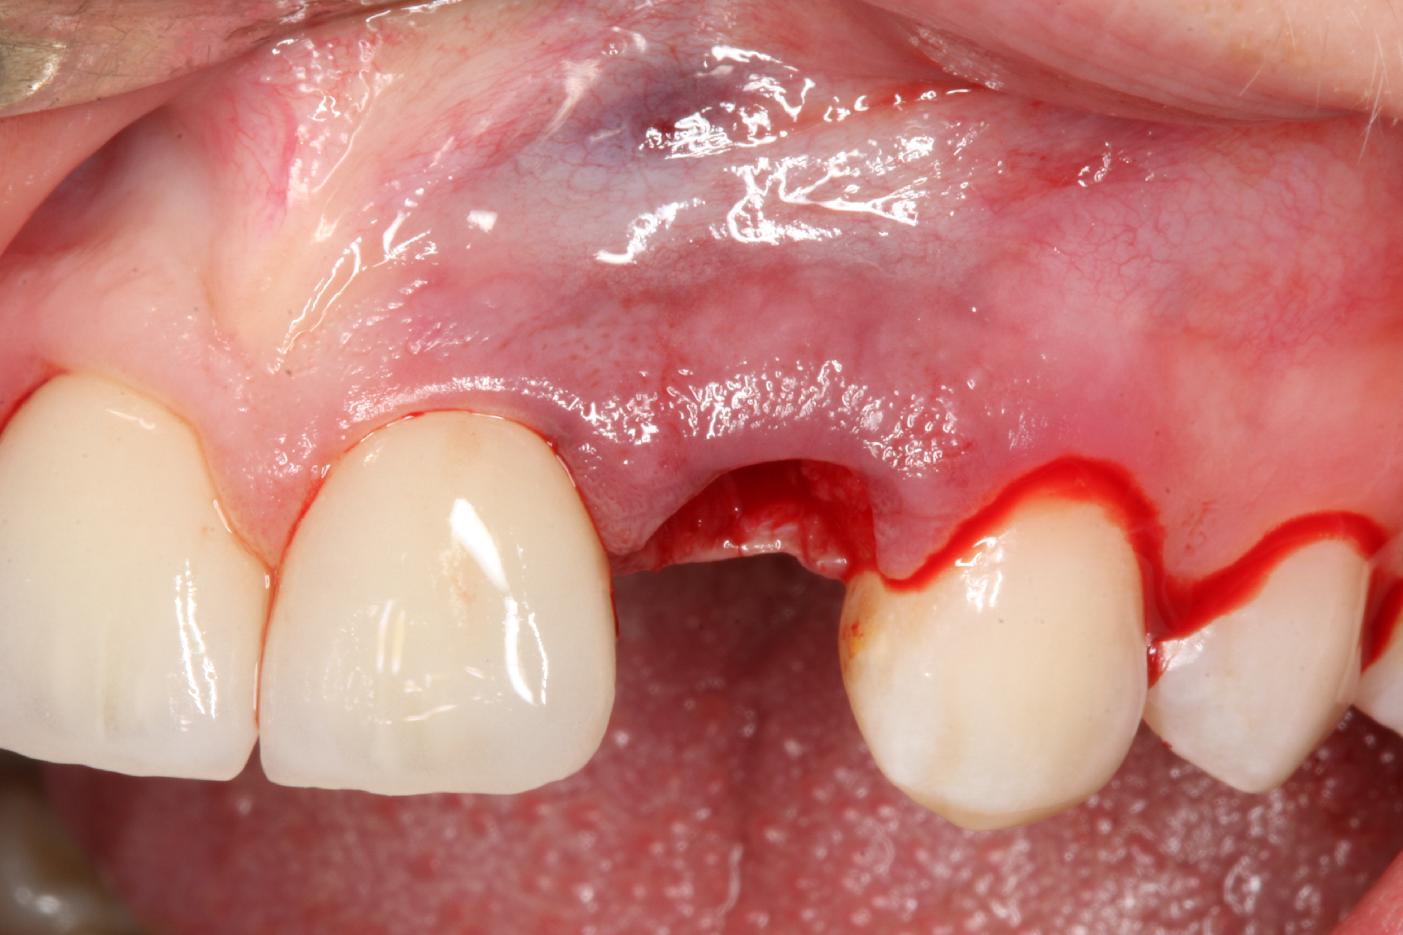

3/12 - Intact socketSoft tissue thickening at immediate implant placement and GBR with mucoderm® and maxgraft® - Dr. A. Puisys